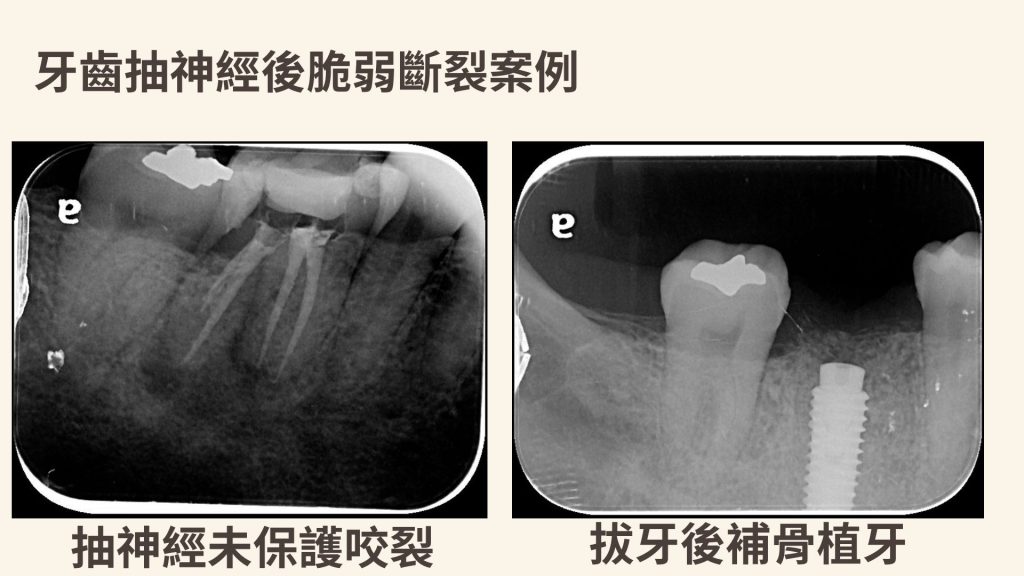

案例解析:L先生的右下第一大臼齒咬裂

治療前:牙齒疼痛疑似有牙根斷裂

治療後:單顆植牙恢復咬合